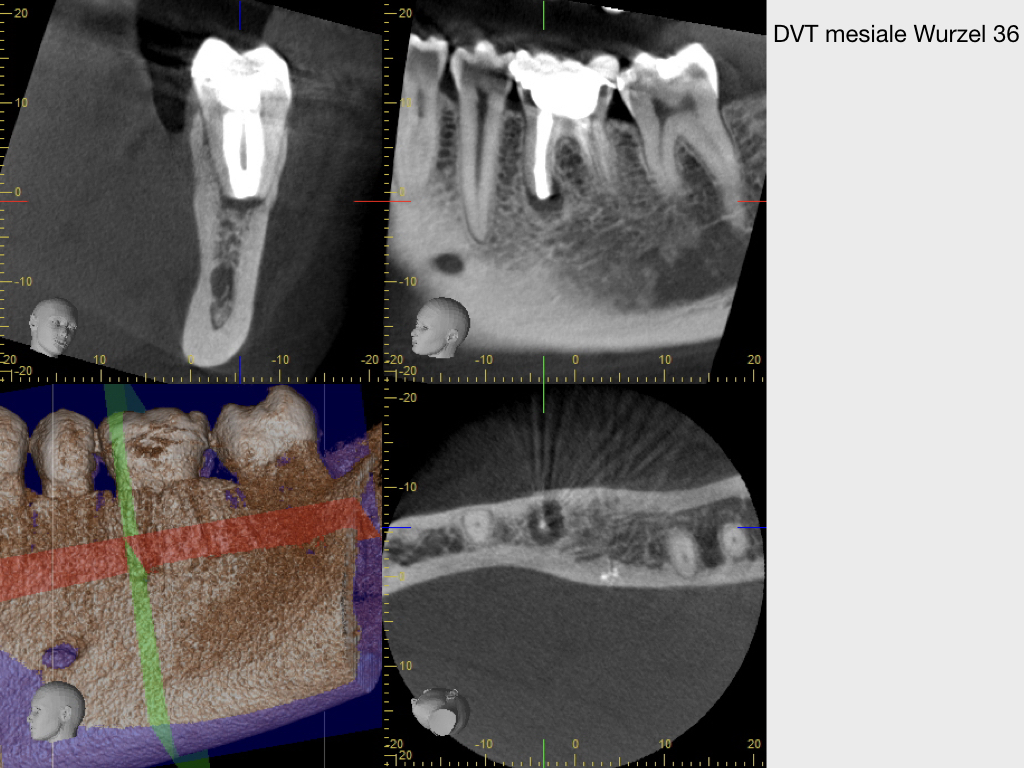

WSR2.003 Veröffentlicht 2. März 2020 am 1024 × 768 in Kurz berichtet – Z.n. WSR – Revision mit minimalinvasivem Zugang